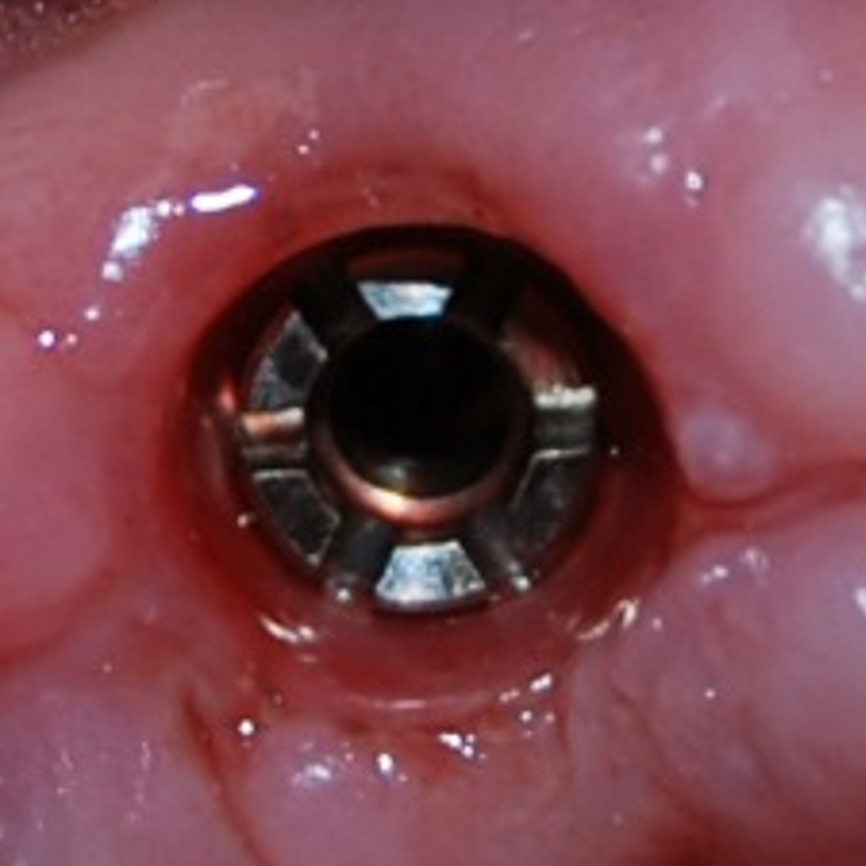

Через три месяца мы сняли коронки с имплантатов, чтобы оценить качество формирования десневого контура:

С этого момента можно перестать переживать — десневой контур сформировался правильно, мы получили достаточный объём и качество окружающей платформу имплантата десны. Можно приступать к изготовлению постоянной протетики. Подрядчиком стала зуботехническая лаборатория French Creative, одна из топовых лабораторий Москвы.